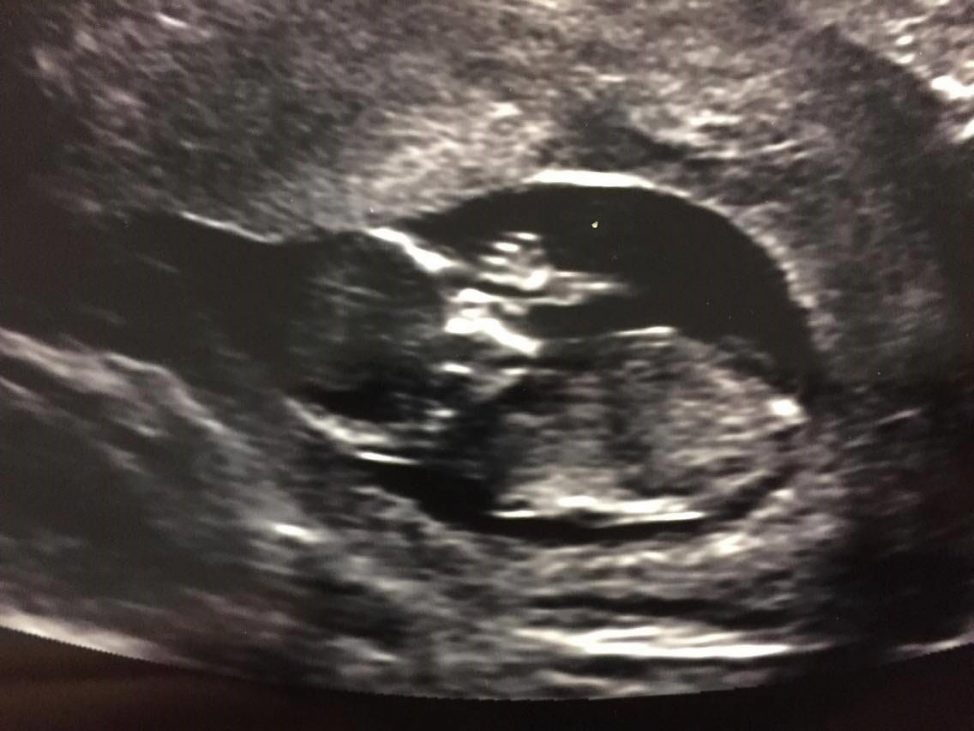

Surrogate Real Talk!

In these articles we interviewed several Surrogates in our program, who are currently pregnant! Follow their journeys as they go through their pregnancies and deliveries! Tell us a little about …